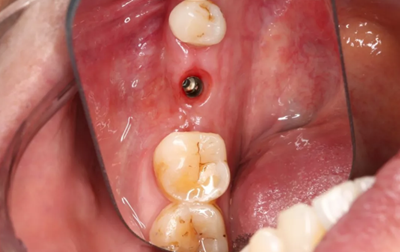

2、術(shù)前口腔內(nèi)照片

46牙烤瓷冠修復(fù),牙周紅腫,叩痛,松2度。骨吸收波及鄰牙,鄰牙牙周情況不佳,45牙松2度,47牙松1度。

(攝于2016年8月31日,反光板協(xié)助拍攝)